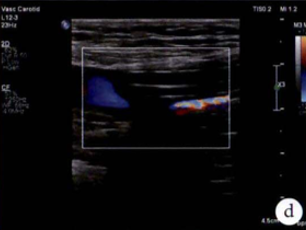

图:d)球囊扩张股浅动脉开口处显像,同时附带血流显像;